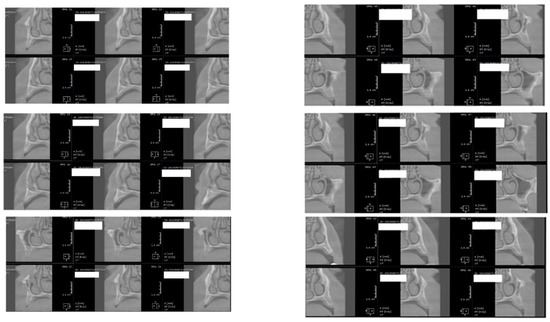

In the subsequent stage of the study, the clinical objectives were met, namely the determination of the radiological bone level, width, height and bone density on Cone Beam Computed Tomographyscans (Planmeca™, Helsinki, Finland). CBCT images were recorded using a tube voltage of 89 kV and a current intensity of 6 mA, the images were recorded with a cylindrical field of view (FOV) of 82 mm both in diameter and height (Figure 1), the voxel size was 0.2 × 0.2 × 0.2 mm and the dental arches were positioned similarly in the FOV, as presented in Figure 2.

Figure 1.

The field of view was a cylinder of 82 mm in diameter and height. The left panel is a 3D section CBCTCone Beam Computed Tomography image, whereas the right panel represents an oblique-section of the same image. F, frontal view, A, Axial View, R, right side view.

Figure 2.

Rendering images showing field of view (FOV) images used in the study. (A) Frontal view, (B) Frontal Bone view, (C) X-ray view.